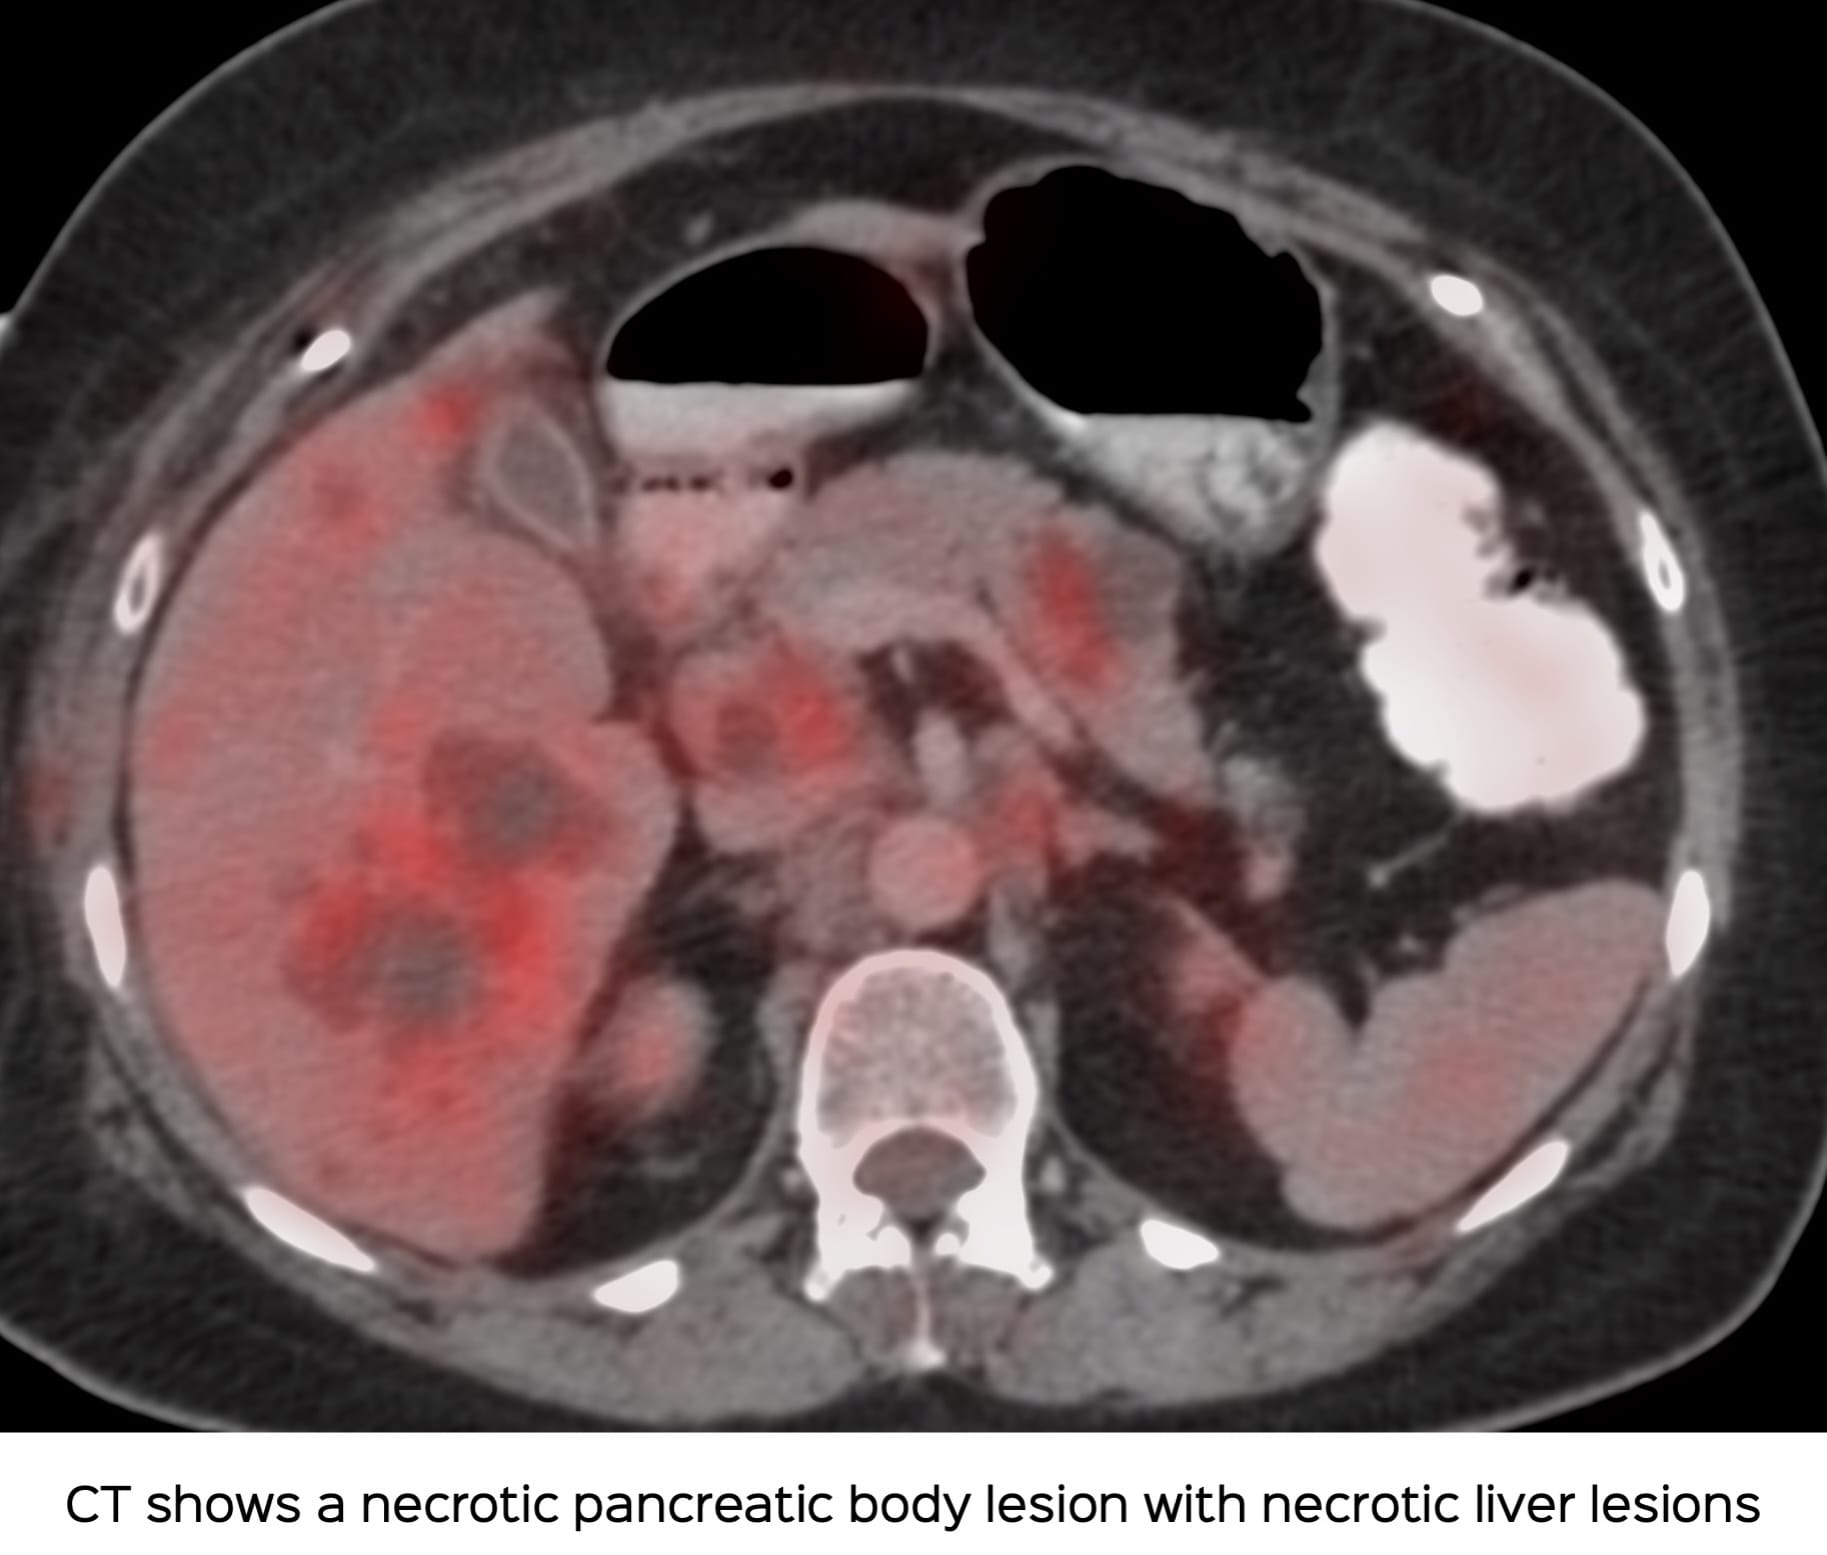

A 55-yrs old presented with a pancreatic body mass and liver lesions.

USG guided liver lesion biopsy was negative and the oncologist wanted a biopsy from the pancreatic body lesion.